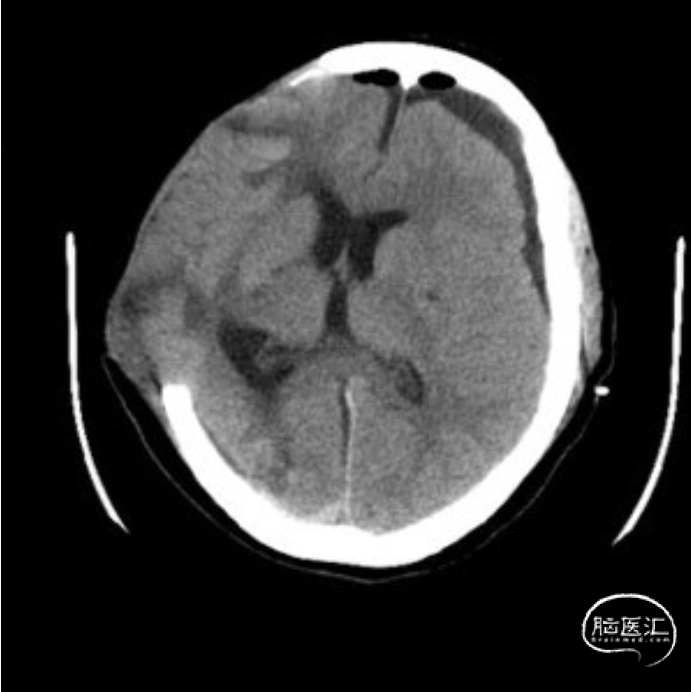

入院头颅CT:右侧颅骨缺失,左侧硬膜下积液,中线右偏明显。